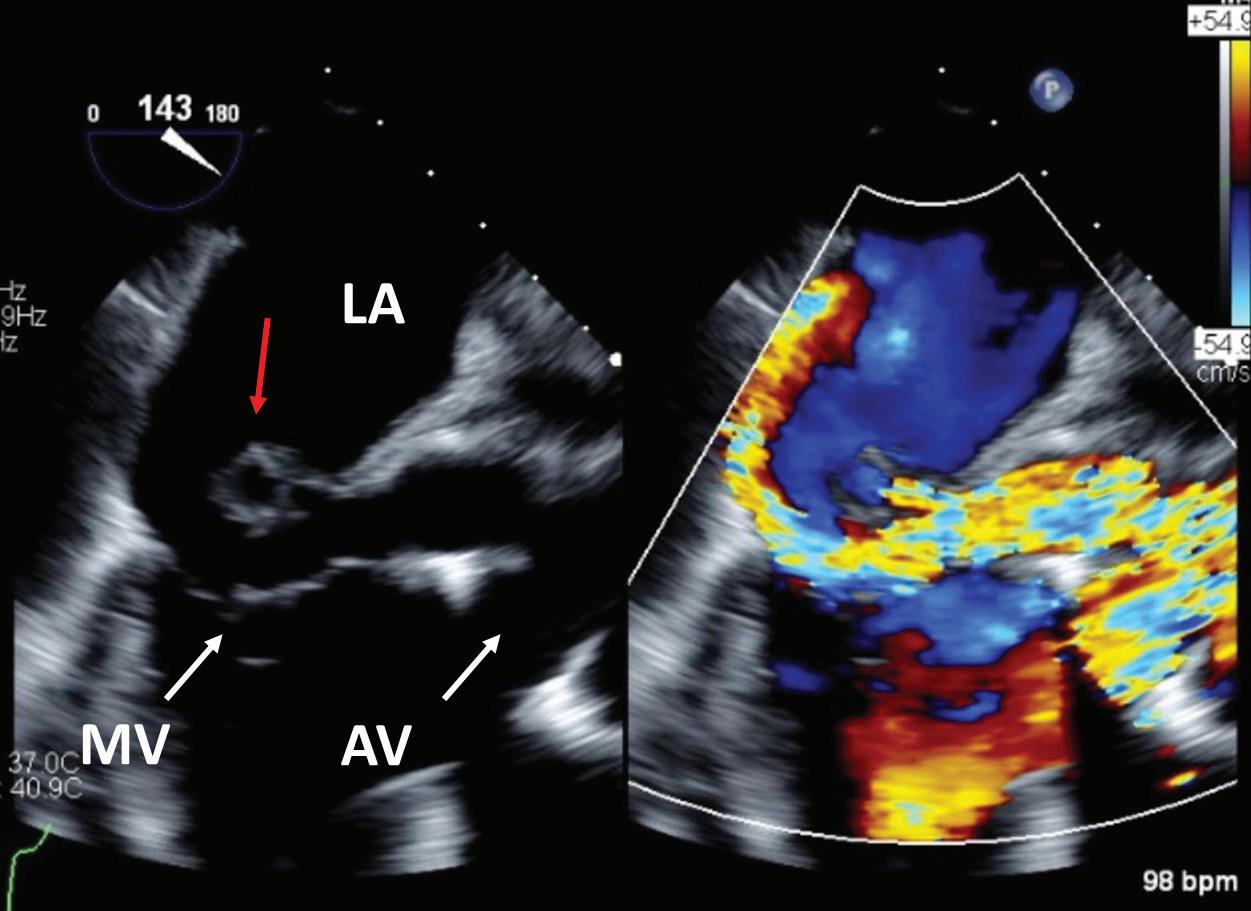

History of Present Illness: A 72-year-old man presented to an outside hospital emergency room (ER) with several weeks of dyspnea on exertion and fatigue. The patient’s presenting vitals in the ER were notable for a heart rate of 90 BPM and a blood pressure of 92/75 mmHg. On exam, he was in no acute distress, had an irregularly irregular heart rate, a harsh systolic murmur loudest at the left upper sternal border, jugular venous distention to his mandible, cool extremities, and 1+ pitting lower extremity edema.

CICU Course: At the outside ER, labs were notable for elevated transaminases and an elevated lactate. A transthoracic echocardiogram

First two panels: large vegetation noted in the right atrium with diastolic flow (red dot) into the right ventricle (RV) noted on transthoracic echo (“RA vegetation” and “Qp/Qs”). On transesophageal echo, a large perivalvular abscess is noted on a mid-esophageal long axis view (“perivalvular abscess”) A left ventricular outflow tract to right atrium fistula is then noted on the mid-esophageal RV inflow-outflow view (“perivalvular fistula”).

EKG demonstrating first degree heart block and left bundle branch block. Inferior vena cava (IVC) view on transthoracic echo demonstrating dilated IVC and likely elevated right atrial pressure. Chest X-ray demonstrating pulmonary edema.

Figure 1B: Acquired Gerbode Defect Due to Endocarditis

(TTE) revealed a tricuspid valve vegetation with moderate tricuspid regurgitation. The patient was transferred to the cardiac intensive care unit (CICU) for further evaluation of tricuspid valve endocarditis.

On arrival to the CICU, labs were notable for a creatinine of 2.4 mmol/l, potassium of 5.5 mmol/l, alanine transaminase of 1,684 U, aspartate aminotransferase of 1,126 µ/l, and lactate of 5.9 mmol/l with a pH of 7.35 on venous blood gas. EKG showed sinus rhythm with a PR interval of 316 ms and a left bundle branch block. A TTE demonstrated severe eccentric tricuspid regurgitation and a large right atrial vegetation. There was also diastolic flow into the right ventricle from an unclear origin (Figure 1A).

Subsequent transesophageal echocardiogram (TEE) revealed a circumferential aortic root abscess with a perivalvular fistula from the left ventricular thrombus (LVOT) into the right atrium (RA) above the tricuspid valve annulus with more flow through the fistula than across the aortic valve (Figure 1A).

• In a patient with shock out of proportion to the suspected valvular lesion, careful attention to hemodynamics should lead to re-evaluation with TEE (Figure 1A).

• Acquired Gerbode defect is a rare complication of aortic root abscesses and can present with AV conduction disease and acute heart failure (Figure 1B).